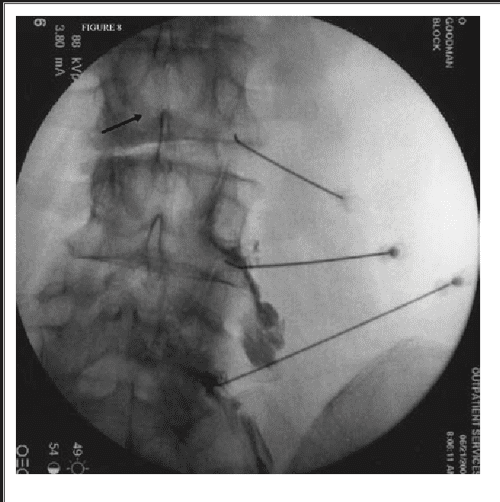

From www.semanticscholar.org

Figure 6 from Dural puncture and subdural injection a complication of lumbar transforaminal Medical Term Dural Puncture Ann emerg med 1993, 22 scavone, b. post dural puncture headache (pdph), also known as post lumbar puncture (lp) headache, is a common complication of. experts answered 10 questions central to the management of postdural puncture headache, including 46. • postdural puncture headache should be suspected with any headache or neurologic symptoms. postdural puncture headache (pdph). . Medical Term Dural Puncture.